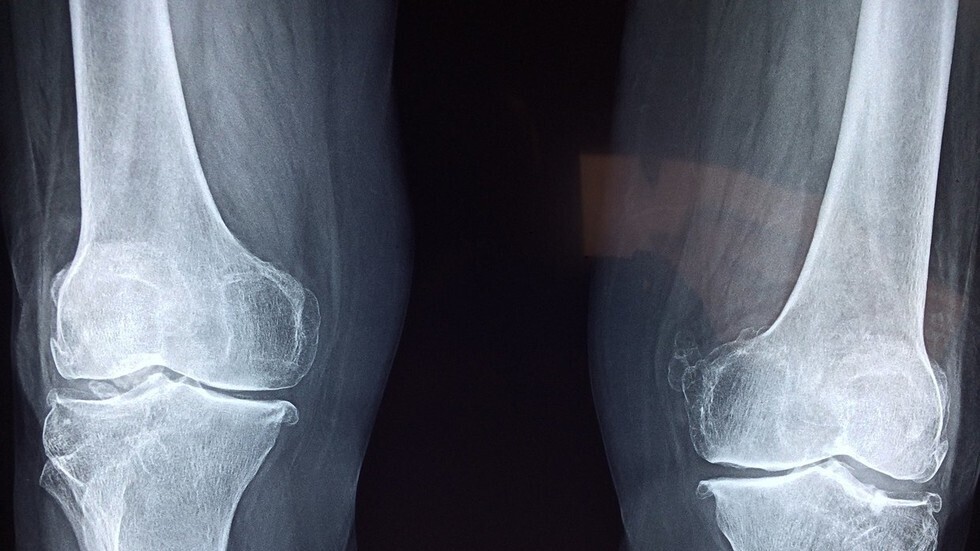

طور علماء من جامعة ساوثهامبتون، تقنية ترى أن جزيئات الذهب النانوية تدخل عظام الإنسان وتجعلها تتوهج، ما يساعد العلماء في العثور على خلايا جذعية ذات قيمة عالية وتعالج العظام.

وعملوا معا لإعادة استخدام المواد النانوية للبحث عن الخلايا الجذعية الموجودة في الهيكل العظمي البشري وإثرائها، والتي يمكن أن تحدث ثورة في علاجات إصابات العظام وربما إصلاح أو استبدال العظام المفقودة.

وهذه الخلايا العظمية لم تُرمّز بعد لوظيفة محددة، وبالتالي يمكن إعادة استخدامها لإنماء وإصلاح أنسجة العظام والغضاريف بهدف إصلاح العظام المكسورة.

ولم يكن من الممكن أن يأتي هذا التطور في وقت أفضل، حيث تشهد العديد من الدول حول العالم شيخوخة السكان، حيث يقدر أن واحدة من كل ثلاث نساء وواحد من كل خمسة رجال، معرضون لخطر كسور هشاشة العظام على مستوى العالم. وتشير التقارير إلى أن كسور العظام وحدها قد تكلف الاقتصاد الأوروبي 17 مليار يورو والاقتصاد الأمريكي 20 مليار دولار كل عام.